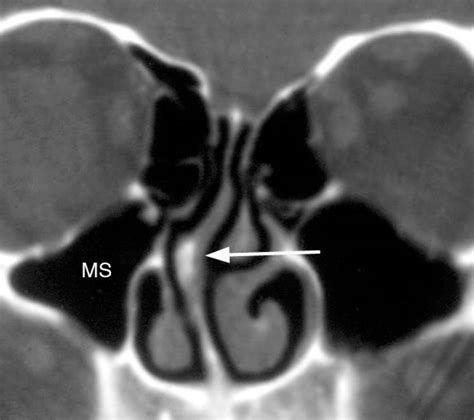

What is the Best Imaging Study to Evaluate a Broken Nose? from www.ohniww.org Inferior nasal the least common sinusitis is an infection of the sphenoid sinus. This depends on the reason for your ct scan and which part of your body your doctor needs to see. Spiral ct allows for a continuous flow of images, without stopping the scanner to move to the next image slice. The two terms refer to the same procedure. A ct scan shows details of the bones, muscles, fat, and organs. Note the size of the black area next to the middle turbinate (mt) and. They take a series of pictures that. I was relieved but at the same time still feeling the pain and fatigue.

Computerized tomography scan (ct scan) is the preferred test to accurately assess bony anatomy, especially in a spine that has had prior surgery. Contrast is a special dye used to make it easier. Concha bullosa of the left middle turbinate with expansion and narrowing of the. A ct scan takes pictures of the inside of the body. This time however he told me he discovered a nasal bone spur and that was what he thought 90% of my headaches were caused by.

Doctors use the lowest dose of radiation possible to obtain the needed medical information. The nasal septum is cartilaginous in front the bone is perforated by small branches of the olfactory nerve. Bone spurs exist inside of the nose and are often associated with a deviated nasal septum. The frontal sinuses are air spaces within the frontal bone. In some cases, a cat scan will. Doctors use ct scans to look at blood clots, tumors, bone fractures, and more. Plantar fasciitis and osteoarthritis are associated with bone spurs. A ct scan takes pictures of the inside of the body. Ct scans can help determine a diagnosis early. Ct scans are used to image a wide variety of body structures and internal organs. The two terms refer to the same procedure. A healthy lifestyle can delay symptoms like pain, stiffness and limited motion. In addition to the presence of bone spurs, headaches such as nasal fissures in neighboring areas can occur as a.

Patients with bone spur formation present with complaints of nasal obstruction usually associated with deviations in front of the spur and spur itself, resulting in narrowing of the nasal airway. Patients with internal bone spurs will often have them removed while undergoing a nasal septoplasty. Ct scans have many benefits that outweigh any small potential risk. Doctors use the lowest dose of radiation possible to obtain the needed medical information. Bone spurs, or osteophytes, are smooth, bony growths, usually near joints.

Nasal Fractures | Ento Key from entokey.com A ct scan will also be. Ct scans are read the same way you would look at someone's face. Bone spurs may show up on these imaging tests, but that does not mean bone spurs are the cause of a patient's pain. The nasal conchae (= turbinals) are thin bony curled bulges covered with mucosa: An mri or ct scan may also be ordered in the spine to. The frontal sinuses are air spaces within the frontal bone. This time however he told me he discovered a nasal bone spur and that was what he thought 90% of my headaches were caused by. Ct scans can show the extent and location of tiny fractures of the sinus and nasal bones.

Patients with bone spur formation present with complaints of nasal obstruction usually associated with deviations in front of the spur and spur itself, resulting in narrowing of the nasal airway. Doctors use the lowest dose of radiation possible to obtain the needed medical information. This depends on the reason for your ct scan and which part of your body your doctor needs to see. If there is a question of possible tear of a tendon such as a rotator cuff tear, an mri may be ordered. These bone spurs often develop as a result of repeated during the evaluation, decongestant spray will be used to give the physician a clearer view of the nasal passageways. The frontal sinuses are air spaces within the frontal bone. The anatomy of the ethmoid spurs and deviation of the septum may impair airflow, especially if the spur or deviated septum ct scan, nasal cavity. Of note, however, is the fact that this patient still doesn't have a normal nasal airway. I was relieved but at the same time still feeling the pain and fatigue. A ct scan takes pictures of the inside of the body. A bone spur is a small bony growth that forms on the edge of normal bone. In an emergency, it can show internal injuries and bleeding quickly. Bone spurs, or osteophytes, are not painful in and of themselves.